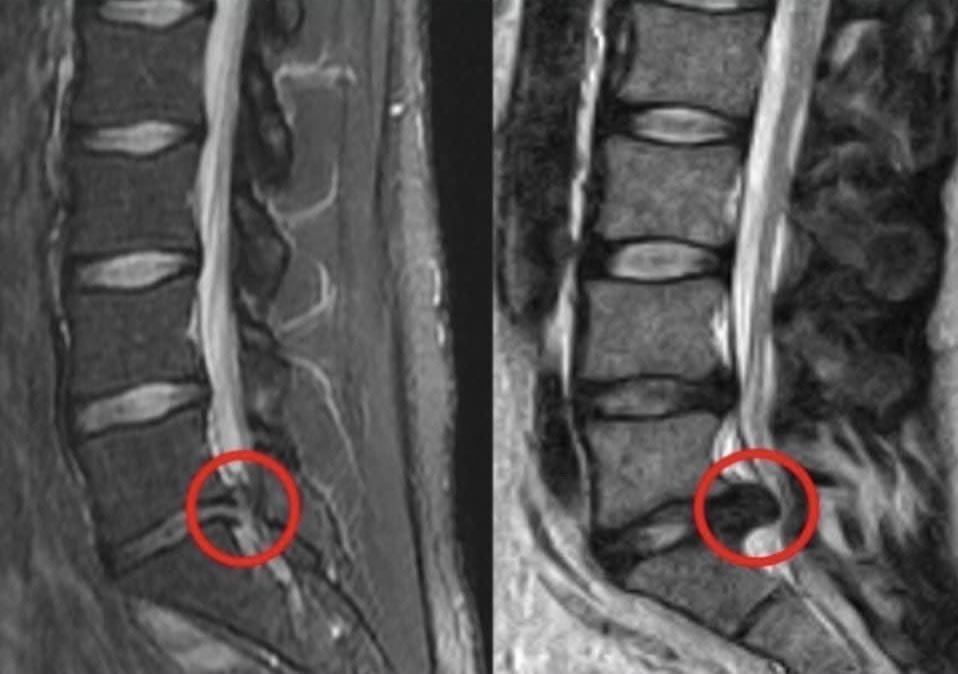

La risonanza magnetica lombosacrale o RMN lombosacrale

invece, esamina i tessuti molli e solidi della zona del rachide compresa tra L1-L5 ed il sacro, anche in questo caso è possibile dividere le regioni, ponendo in analisi una sola porzione; tale tecnica è necessaria per indagare l’origine della sciatalgia cronica da ernia discale e nella diagnosi di difetti della colonna come la spina bifida o la presenza di cisti perineurali.